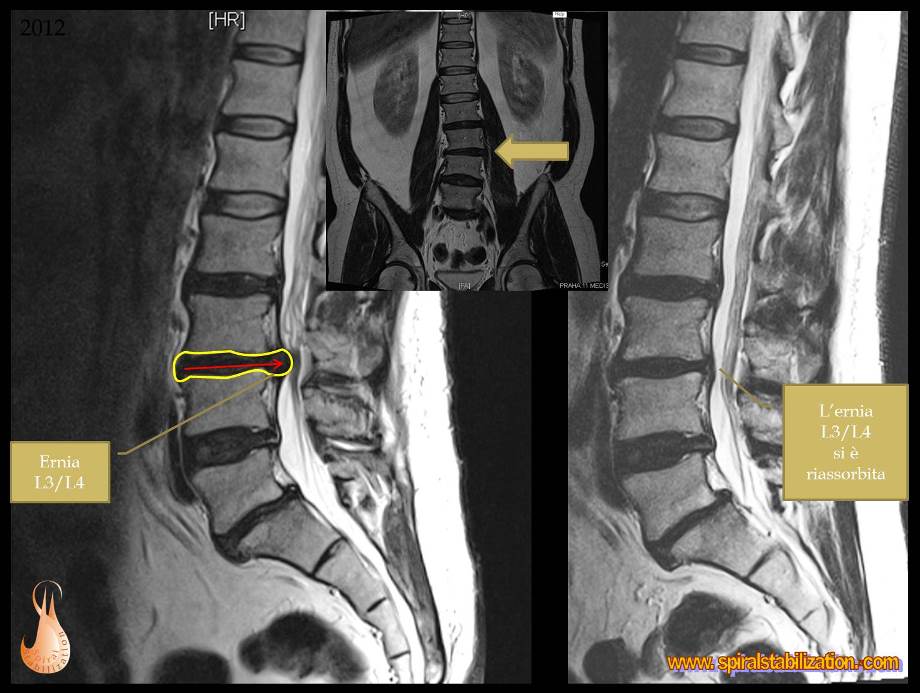

1 - Ernia L3/L4

B - 1 - 1 -1

Ernia del disco L3/L4